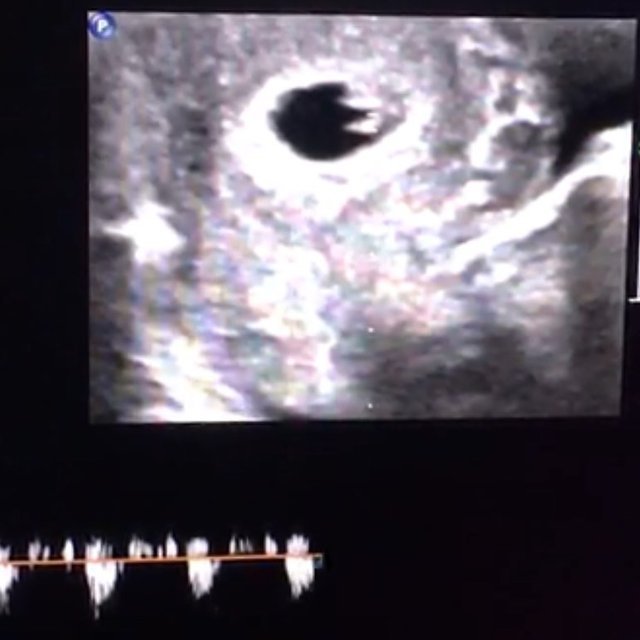

Ultrason görüntülerini yayınlayan Bali, paylaşımına "Biz çok güçlüyüz. Anne-evlat dağları aşarız. Dua edin tansiyonum düzelsin tek ricam bu dua... Allah büyük. Çok zor bir hamilelikmiş bu. Sizden ricam; bol dua" sözlerini eklemişti.